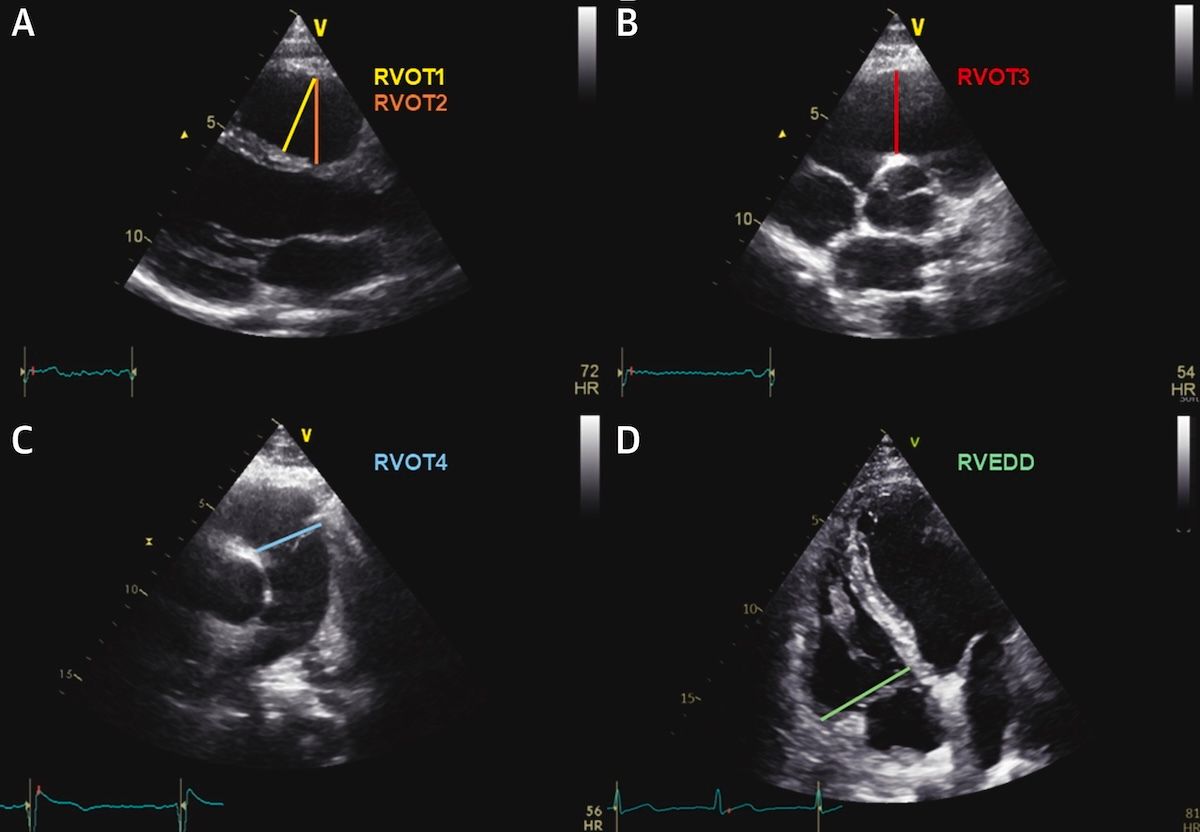

El diámetro del TSVD es un marcador sencillo, robusto y clínicamente útil en la miocardiopatía arritmogénica del ventrículo derecho, muy superior a parámetros más complejos como el strain del VD de pared libre. Una medida sencilla con un gran valor … ¡a medirla que es muy fácil!

Diámetro del tracto de salida del ventrículo derecho para la predicción de eventos en la miocardiopatía arritmogénica del ventrículo derecho 👓 https://t.co/atXLluMXu2 ◀️ Falta definir mejor cómo integrar el diámetro del TSVD en calculadoras de riesgo específicas de MAVD, junto a